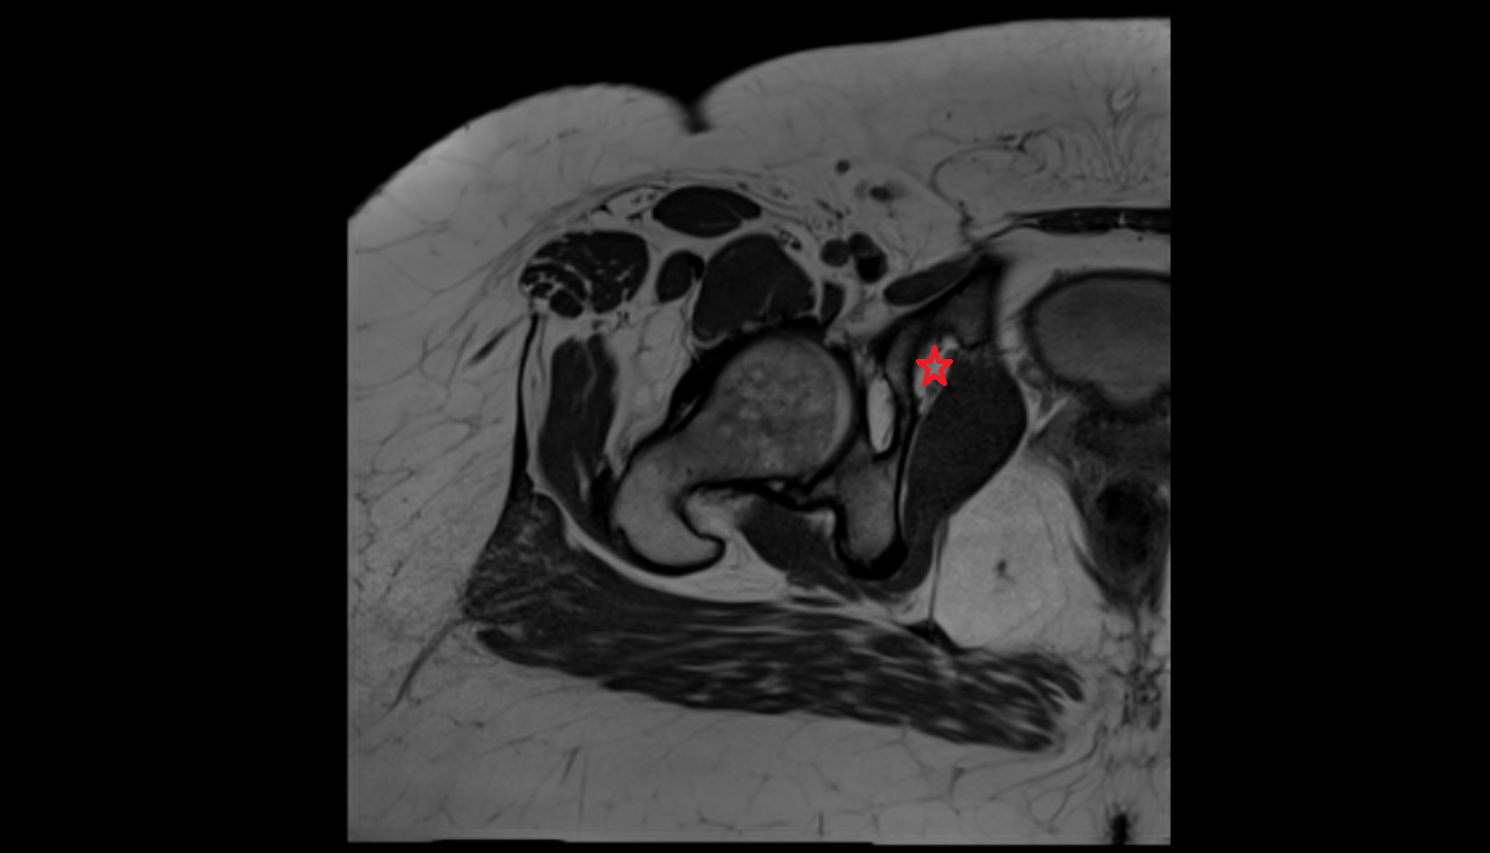

- Peripheral zone of prostate

- Anterior Fibromuscular Stroma of prostate

- Central zone of prostate

- Transitional zone of prostate